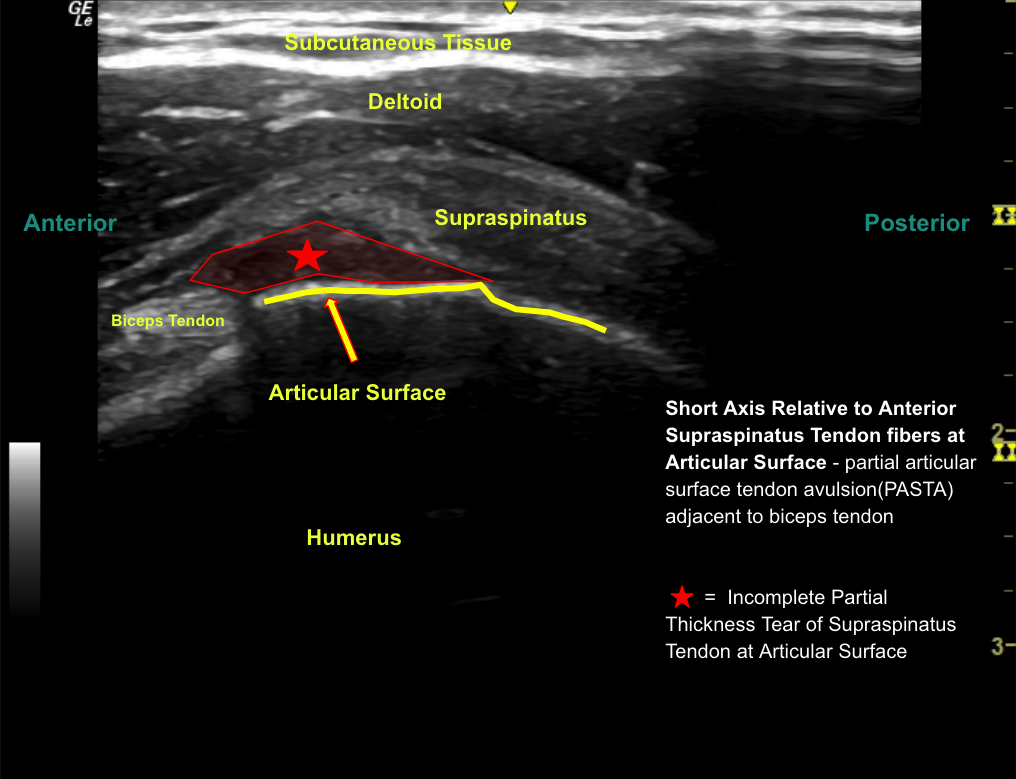

Labeled short axis view of the anterior supraspinatus tendon at the articular surface with a small anechoic defect at the insertion, lateral to the long head of biceps tendon consistent with a partial-thickness partial-width articular sided supraspinatus tendon tear.

Unlabeled short axis view of the anterior supraspinatus tendon at the articular surface.